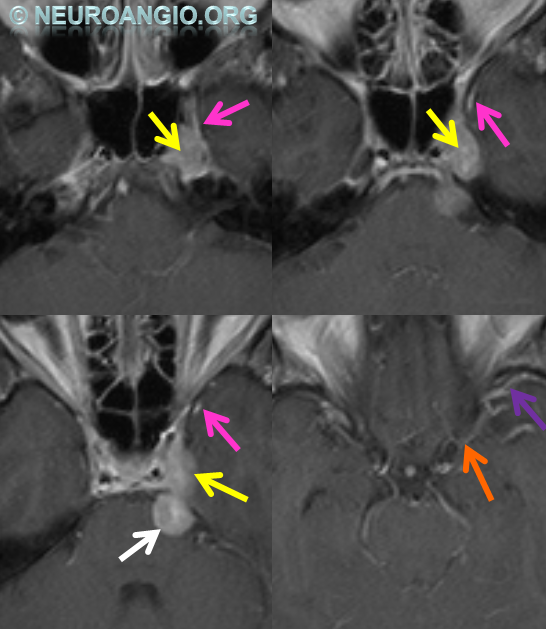

Some arrows. Open white arrows — septal veins on the medial aspect of frontal horn. Thick white arrows — longitudinal caudate venous arcade. Black arrow — direct lateral vein, prominent because of hypoplasia of the posterior segment of the left longitudinal caudate vein. Thin white arrows are transverse/ medullary veins

Below is an example of as large an inferior sagittal sinus (white) as one is likely to ever see under non-pathologic circumstances. Why is this sinus so large? Again, the answer is that veins are like rivers — the inferior sagittal sinus happens to be receiving a completely benign, nonpathologic mesial anterior frontal vein (blue arrows). However, the increased inflow into the Galen system has likely resulted in alternate drainage of the basal vein (purple) into the superior petrosal sinus via the lateral mesencephalic vein (black) — see deep venous system and veins of posterior fossa pages for more info. Also notice a large emissary vein (pink)